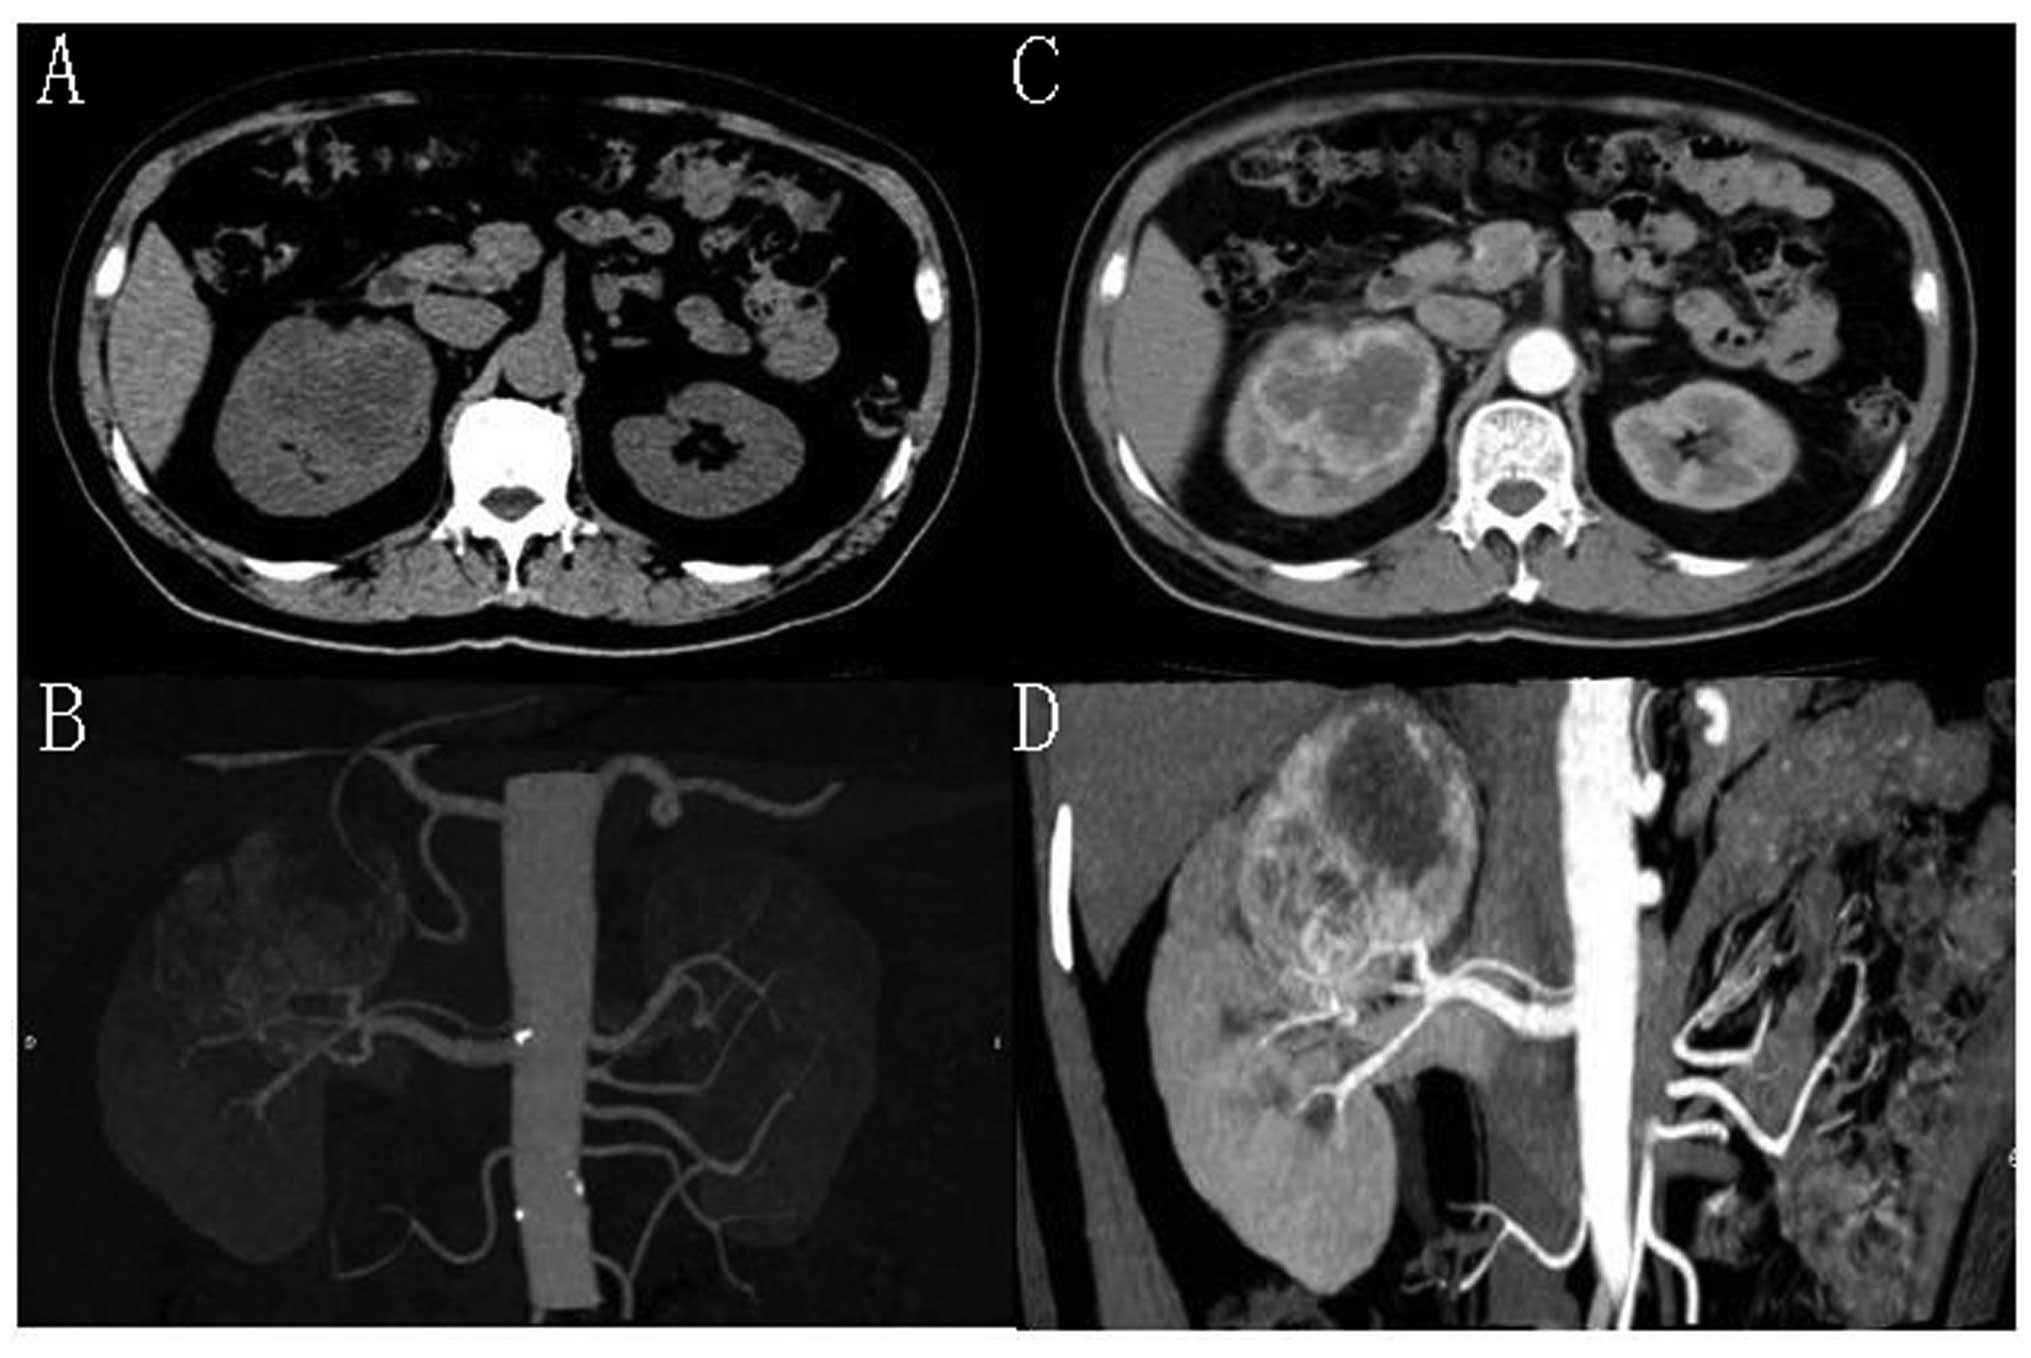

Haemangioblastoma is a benign tumour which generally occurs in a relatively restricted area of the central nervous system. Renal haemangioblastoma are extremely rare. We report a rare case of renal haemangioblastoma occurring in a 61-year-old male with a solid mass, which was detected during a routine examination. The patient was asymptomatic and abdominal computed tomography (CT) revealed a solid mass in the right kidney. No definitive preoperative diagnosis could be established. Surgical resection of the tumour revealed sporadic renal haemangioblastoma by pathological examination. The patient was followed up at 1 year without any problems. We also present a supplementary review of previously published cases and literature.

Figure 1